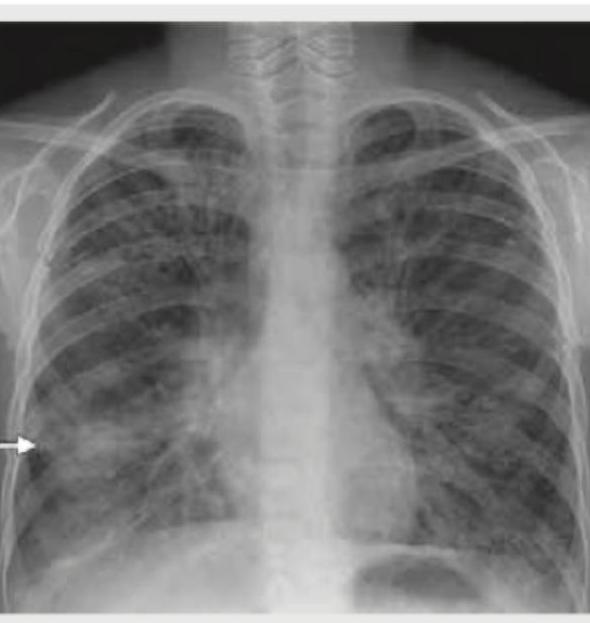

An adult undergoes multiple FFP transfusions for excessive bleeding after cardiac surgery and develops respiratory distress. CXR done is shown below. What does it indicate?

Explanation: ***TRALI*** - The chest X-ray shows **bilateral pulmonary infiltrates** and **pulmonary edema** and the patient had multiple **FFP transfusions** followed by respiratory distress, which is highly suggestive of **Transfusion-Related Acute Lung Injury (TRALI)**. - TRALI is characterized by acute respiratory distress with **hypoxemia** occurring within 6 hours of transfusion, in the absence of other risk factors for **Acute Lung Injury (ALI)**. *Volume overloading of heart* - While fluid overload can cause pulmonary edema, the severity and rapid onset of distress after transfusion, coupled with the bilateral infiltrates, point more specifically to TRALI rather than isolated volume overload, especially in the context of FFP. - Cardiogenic pulmonary edema typically presents with **cardiomegaly** and signs of **heart failure**, which are not explicitly described or obviously seen as the primary cause in the given scenario and image. *Mendelson's syndrome* - Mendelson's syndrome, or **aspiration pneumonitis**, results from the inhalation of acidic gastric contents, leading to chemical pneumonitis. - This typically occurs in patients with impaired consciousness or those undergoing procedures that compromise airway protection, and there is no information in the vignette to suggest aspiration. *Pneumomediastinum* - Pneumomediastinum indicates the presence of **air in the mediastinum**, which would appear as radiolucent streaks outlining mediastinal structures on a CXR. - The image primarily shows diffuse bilateral infiltrates and pulmonary edema, rather than free air in the mediastinum.